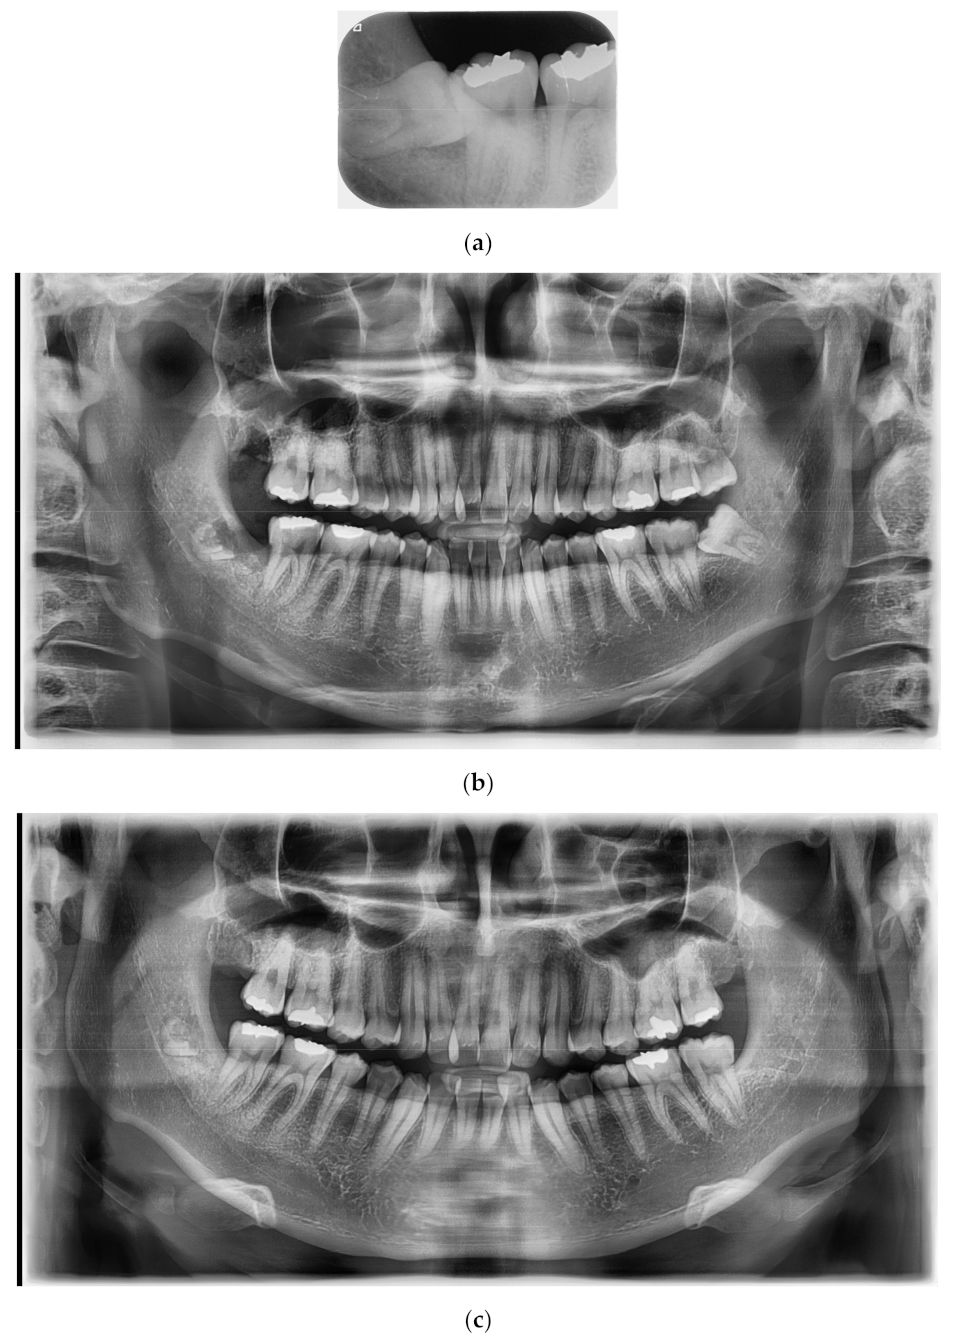

A 25-year-old female patient without systemic diseases had the right mandibular wisdom tooth extracted three years ago due to mesioangulation, which caused pain and sensitivity to its adjacent second molar in addition to recurrent inflammation in the gingiva and pericoronitis (Figure 2a).

The main clinician (Kim) decided to perform a coronectomy to avoid any risk of nerve damage in this young patient who had odontophobia; therefore, the surgical procedure was fast and without bone cuts. Using CBCT, the position of the apical third of the roots was confirmed to be very close to the inferior alveolar nerve.

After 14 days, the patient was recalled for suture thread removal, where she was free of pain (VAS score “2”) and showed no sign of fear while in the dental office (Figure 2b). Three years later, the patient came again to the dental clinic for a dental check-up and for the extraction of the left mandibular wisdom tooth, and she reported no sign of pain or disturbance in the area of the right mandibular wisdom tooth. Figure 2c shows the complete formation of the alveolar cortical bone.

Figure 2. (a): Right mandibular wisdom with pain and sensivity due to pericoronitis. (b): X-ray after 14 days from the coronectomy. (c): OPT after three years of follow-up.